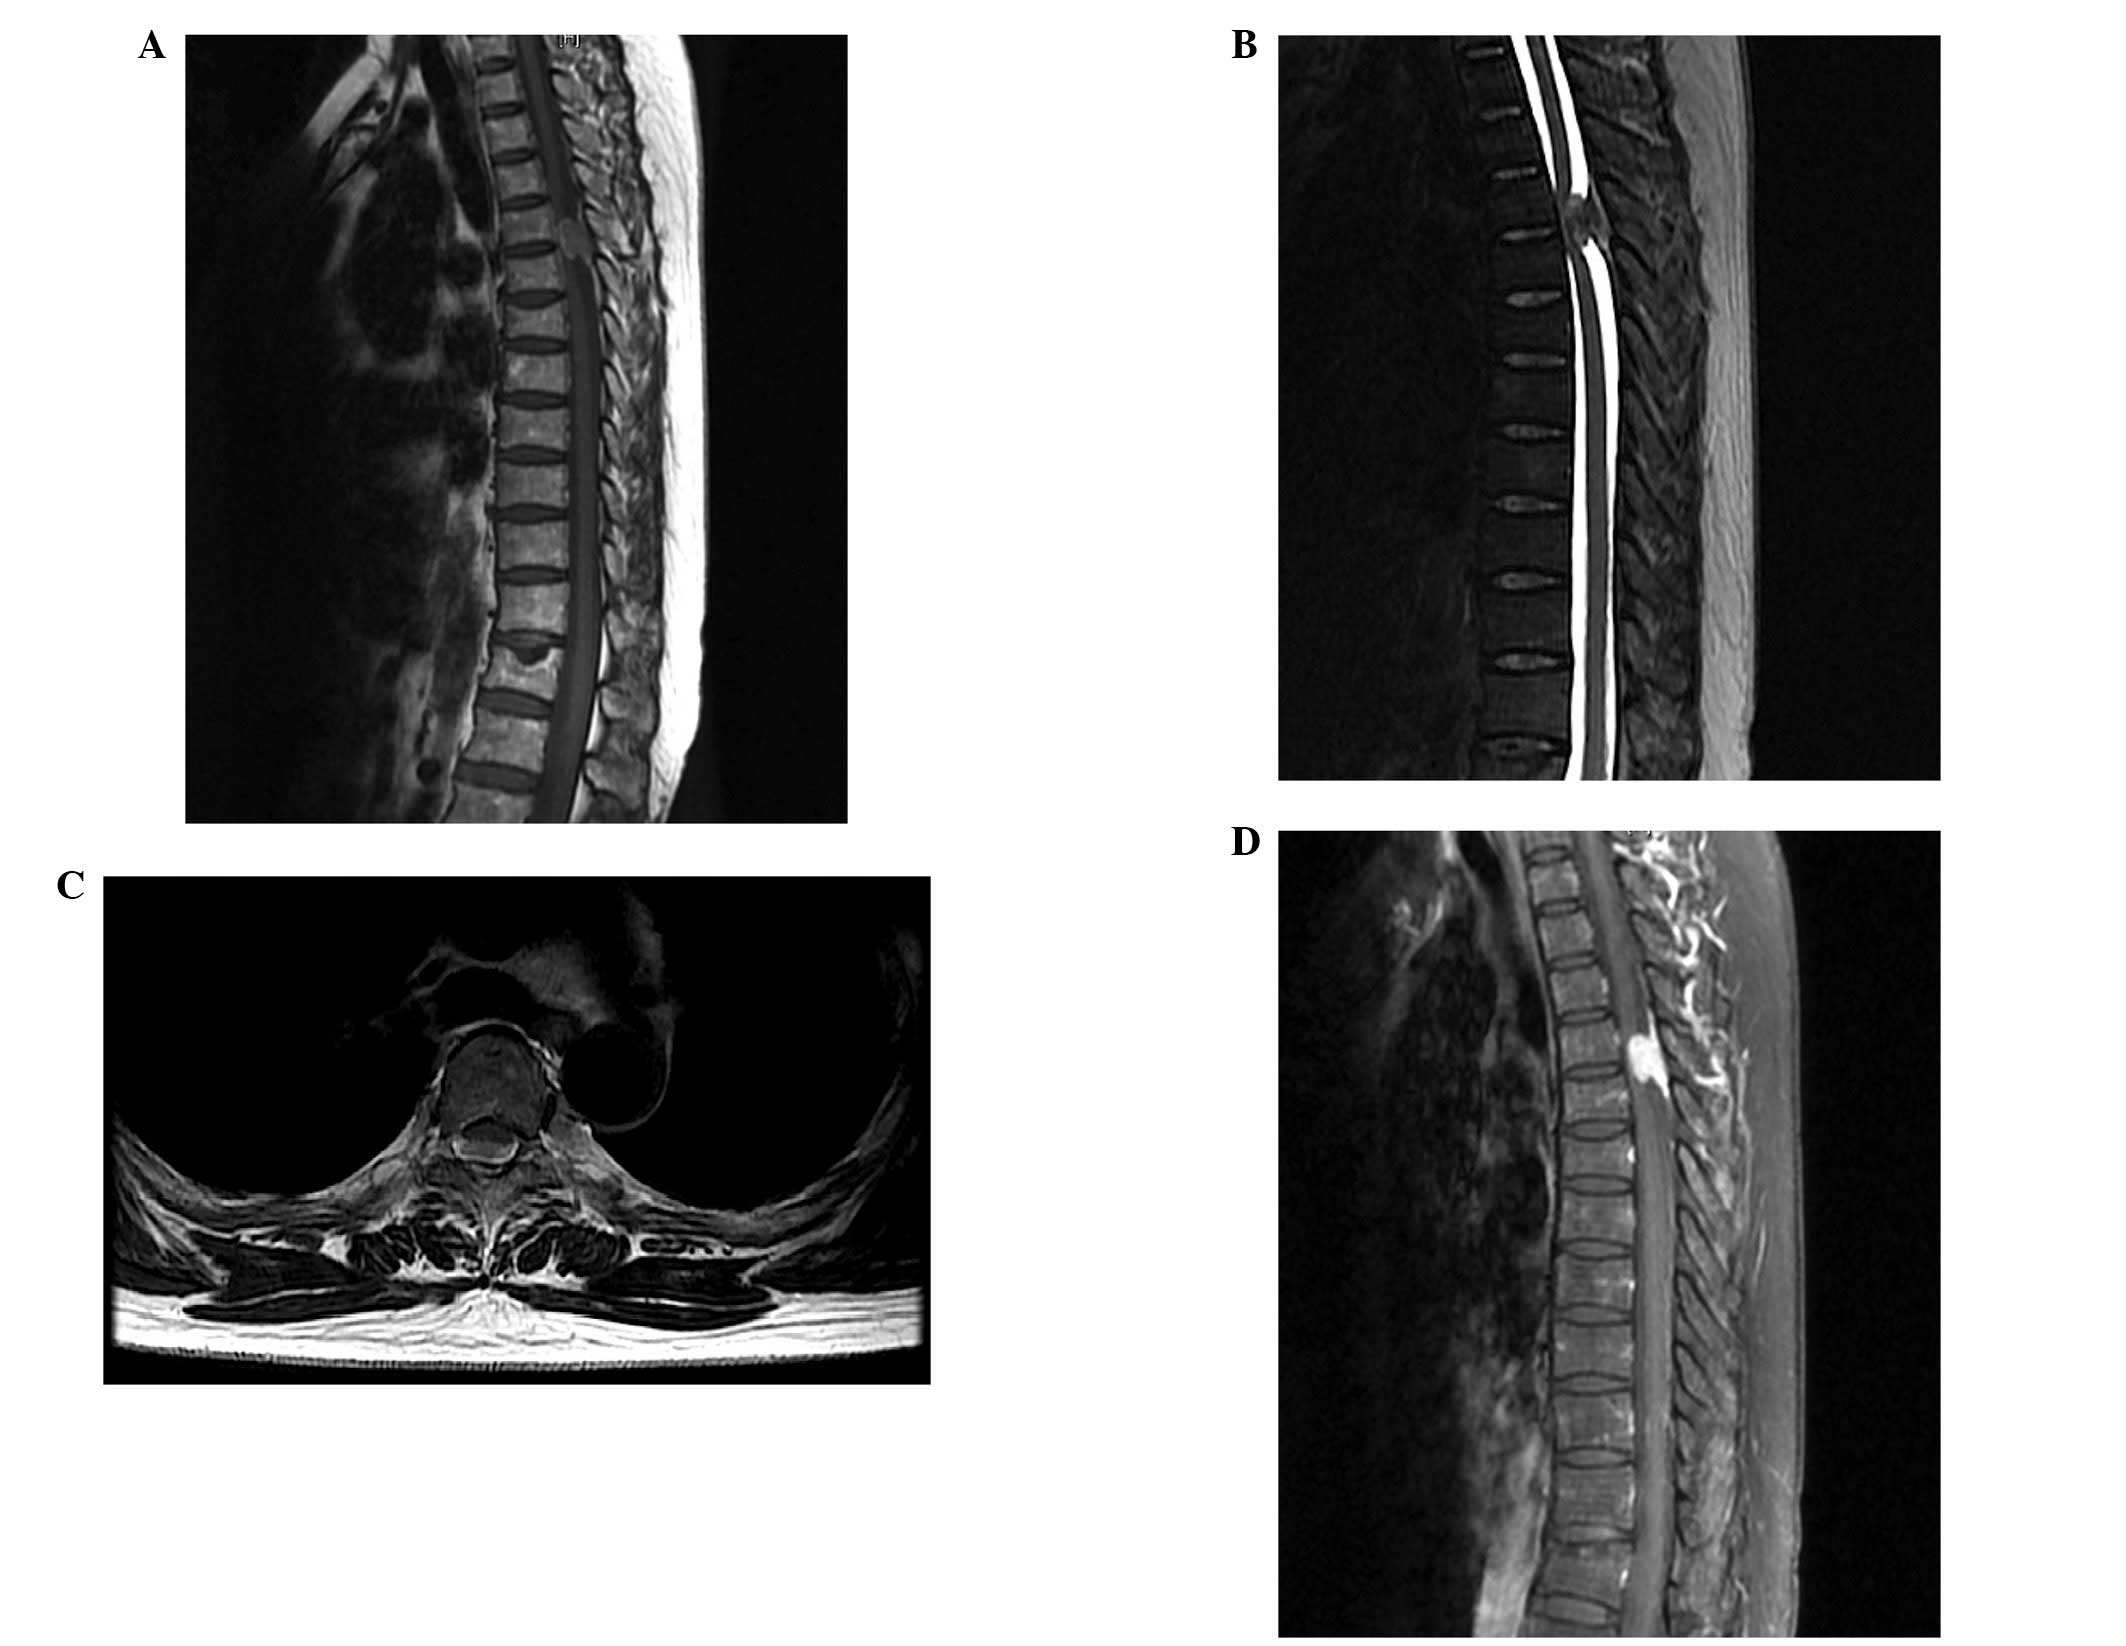

A 57-year-old female was admitted to the Clinical Medical College of Yangzhou University (Northern Jiangsu People’s Hospital, Yangzhou, China) in December 2012 with a history of bilateral lower-extremity numbness and back pain for one month. One week prior to admission, the patient noticed a more marked tingling sensation and progressive weakness in the lower extremities. Upon admission to hospital, a neurological examination revealed hypoesthesia below the T8 level and progressive weakness (grade IV) of the bilateral lower extremity. The deep-tendon reflexes of the lower extremity were weak and accompanied by uroschesis. The Babinski sign was positive on the two sides. MRI scans of the thoracic spine revealed a space-occupying mass (size, 17×10 mm) with an obvious dural tail sign at the T4–T5 level (Fig. 1). The margins of the mass were indistinct and the adjacent dural exhibited local incrassation and compression of the spinal cord. The lesion was initially diagnosed as a complex spinal meningioma and surgery was performed on the patient.

With regard to radiological examination, MRI scans are commonly used to identify different spinal lesions. The typical pattern of spinal melanoma observed using MRI, includes signal hyperintensity on T1-weighted images and signal isointensity or hypointensity on T2-weighted images. These signal characteristics are inconsistent as the MRI signal depends on the presence of melanin, intratumoral hemorrhages and fat deposits, which complicates the majority of spinal melanoma images. MRI scanning aids diagnosis, however, it does not specifically differentiate between primary melanoma and other malignant lesions. The signal characteristics of MRI may easily lead to an erroneous diagnosis. It is important for surgeons to make an accurate diagnosis and be aware of the limitations of the diagnostic value of MRI. In the present case report, enhanced MRI revealed an obvious dural tail sign, which is a classic characteristic of meningioma. However, T1-weighted images with hyperintensity and T2-weighted images with hypointensity are typical features for melanoma, and atypical for meningioma. Therefore, it is difficult to exclude the diagnosis of spinal meningioma prior to surgery, as intratumoral bleeding may result in an uneven hyperintensive signal in T1-weighted images. In the present case report, the final diagnosis of the patient required further investigation using methods other than MRI.